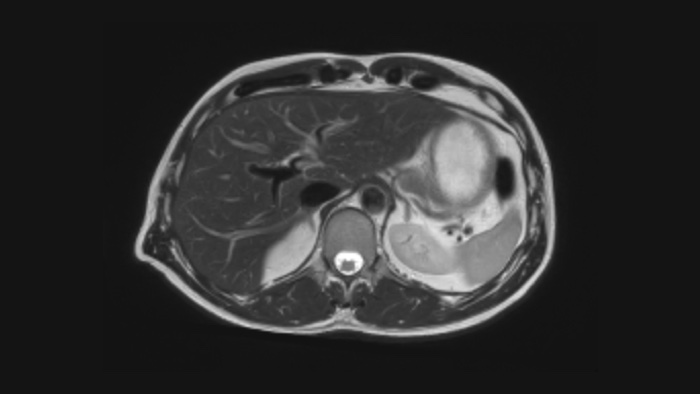

Diagnostic confidence Expand your imaging capabilities in all clinical areas. See how your peers are benefiting.

Speed & Comfort Provide up to 40% reduction in breath holds, with virtually equal image quality4.

This innovative solution offers many clinical, operational and financial benefits.